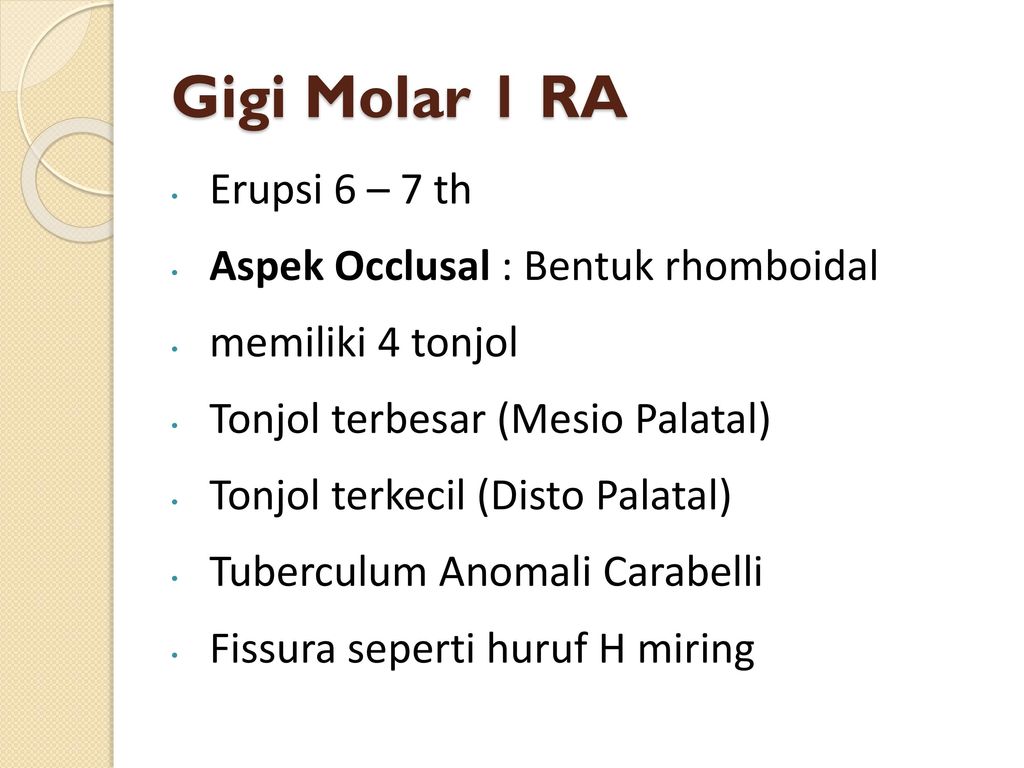

Morfologi Gigi Permanen Rahang Atas - ppt download

Morfologi Gigi Permanen Rahang Atas - ppt download

9. morfologi gigi permanent rahang atas

9. morfologi gigi permanent rahang atas